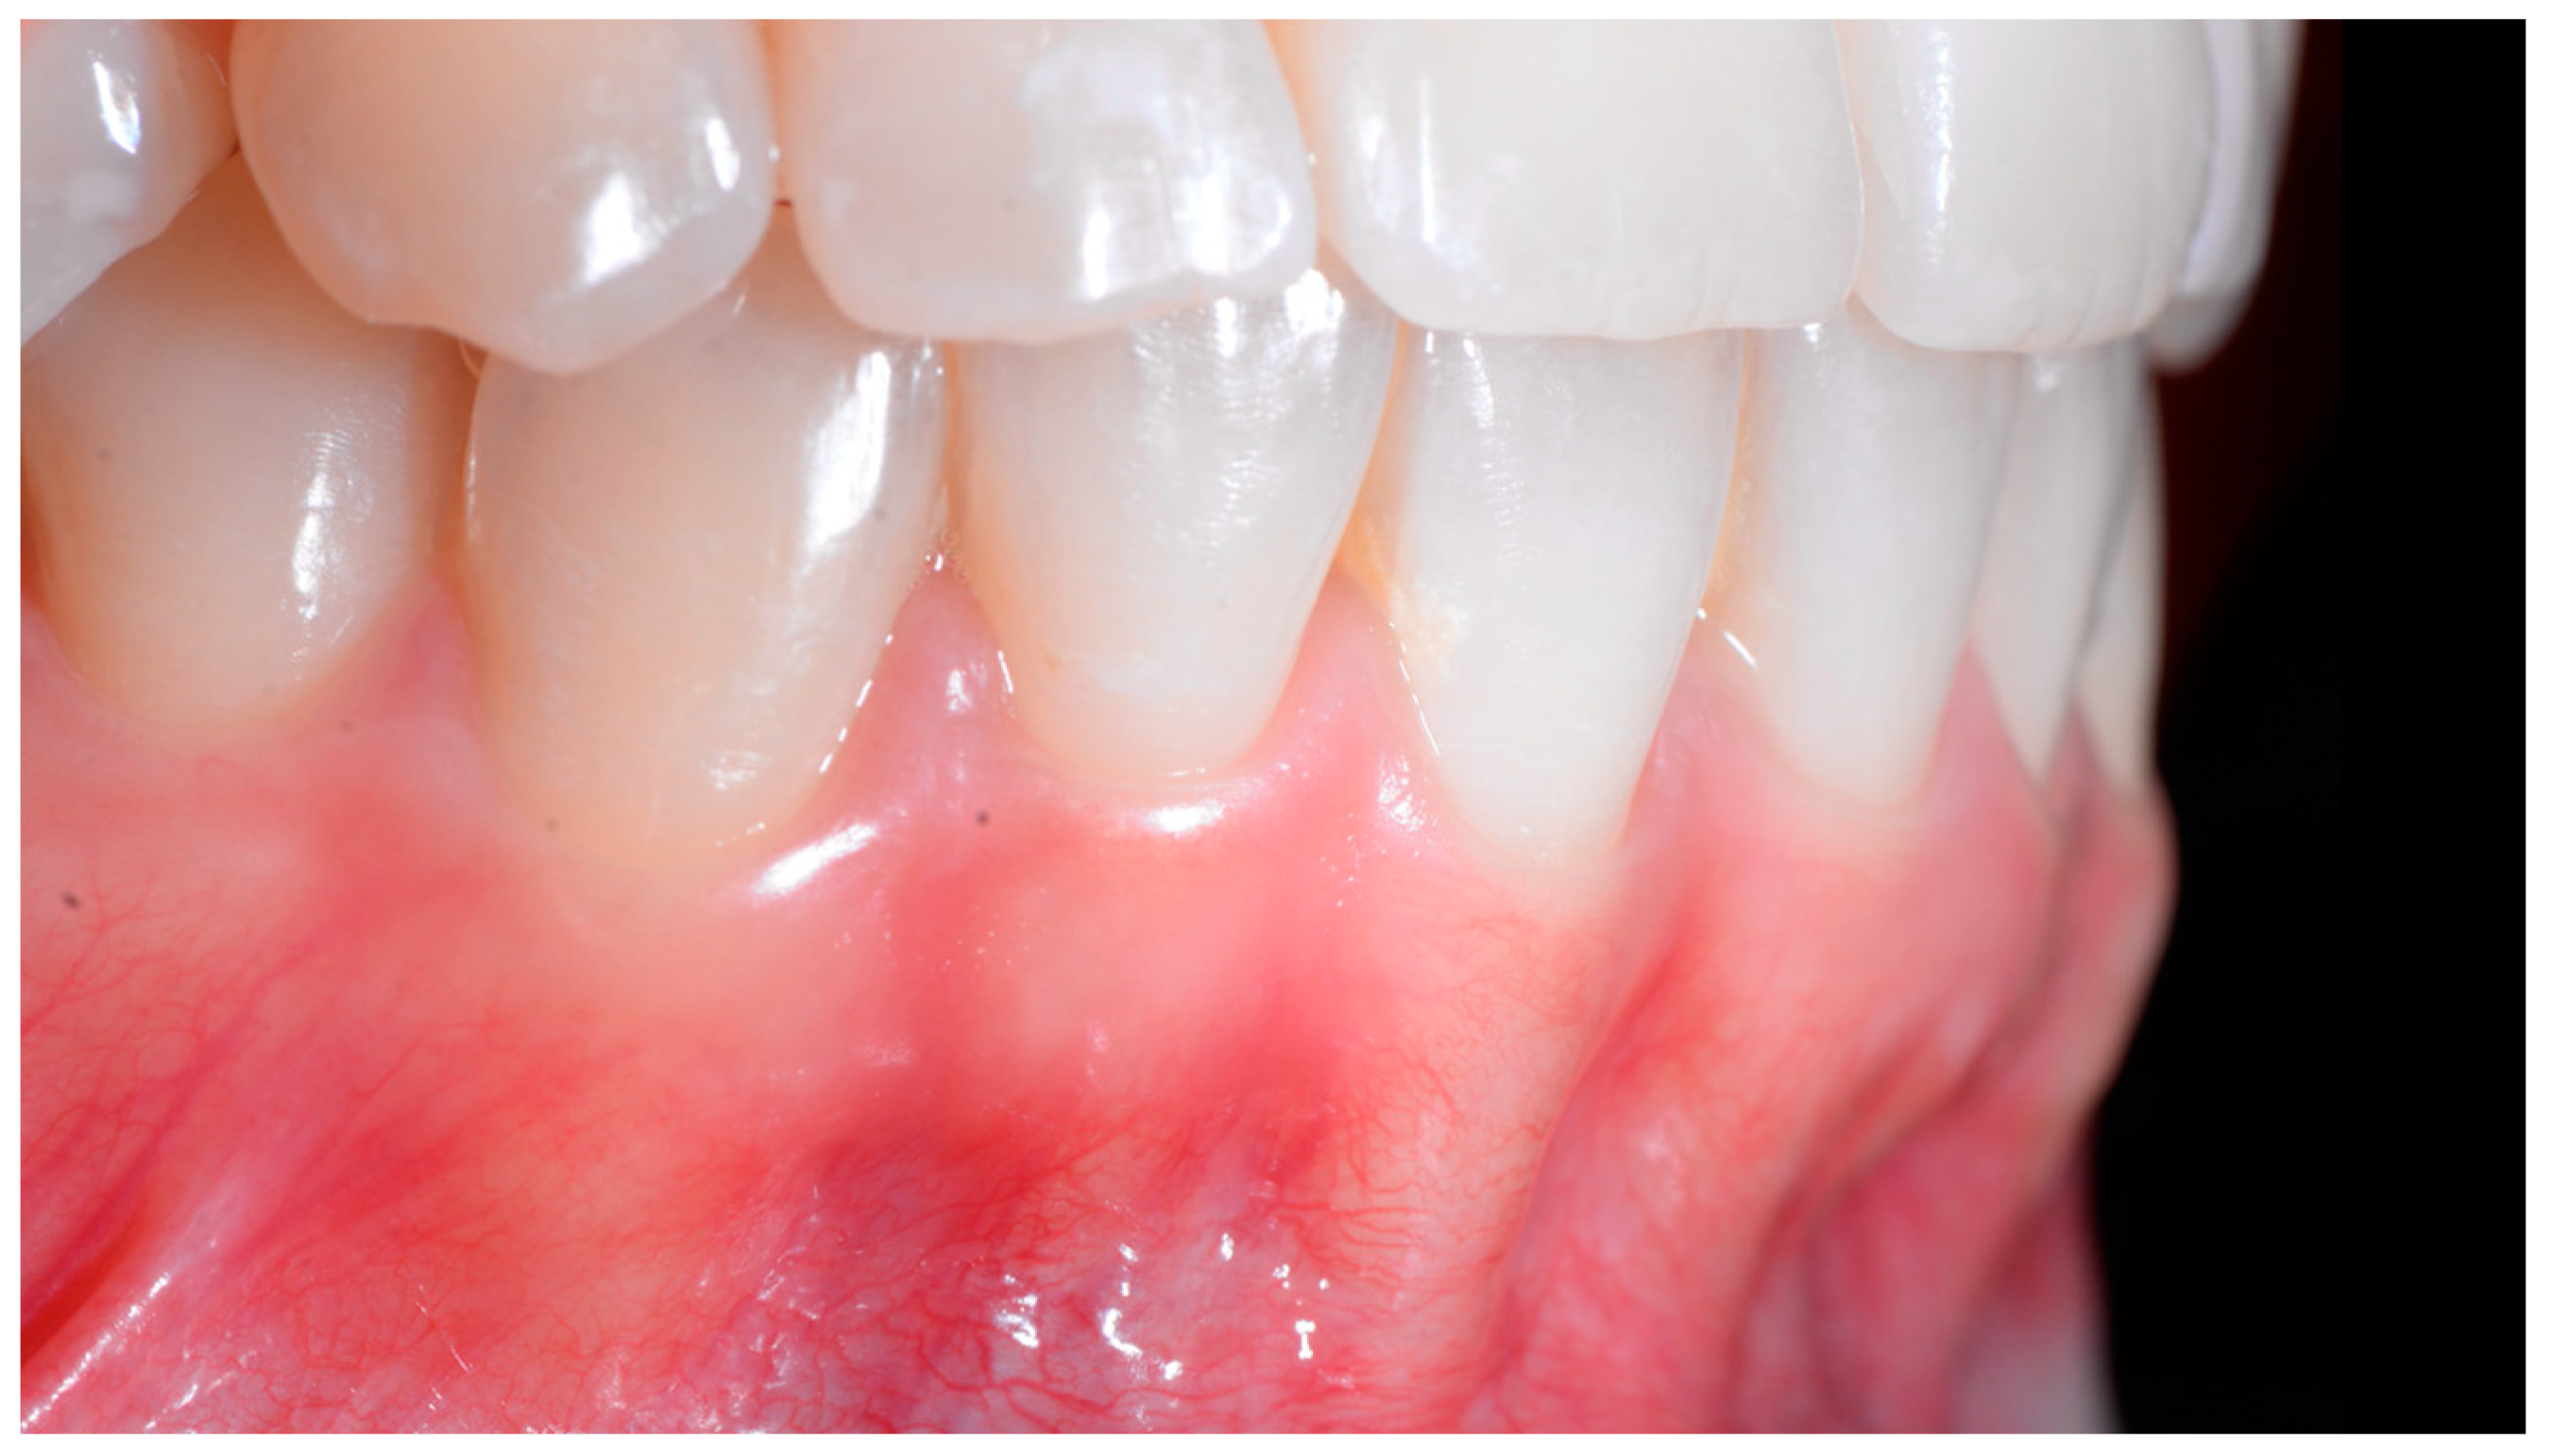

In Figure 2, the following can be observed: a difference in gingival margin height between 41 and 31, a difference in height of the incisal edges of 41 compared to the adjacent teeth, and the onset of gingival recession on 41 associated with the visibility of a vestibular arch corresponding to its root.

Figure 2.

Early wire syndrome. Frontal views.

In the lateral view (Figure 3), the prominence of the root of 41 was confirmed.

Figure 3.

Early wire syndrome. Lateral view.

When the displacement due to wire syndrome is minimal, the result is a slight displacement of the affected tooth, with the maintenance of contact points but the loss of tooth neck (cervical margin) alignment and the appearance of discrete gingival recession (Figure 1). In the lateral view, the displacement of the tooth is visible and can be objectified via the digital palpation of the root. In the occlusal view, the incisal edges are no longer completely aligned. Over time, the more the root becomes displaced, the thinner the gingiva becomes and the more the attachment worsens, first on the entire face of the tooth (vestibular or lingual) and then in the interdental area. Clinically, this results in increasingly wide and deep gingival recessions and the loss of tooth alignment (Figure 2). Eventually, interdental spaces appear and the displacement of the roots from their sockets is major. Therefore, in the presence of very large tooth displacements (end of the WS process), the orthodontic retainer becomes detached or breaks (Figure 3).